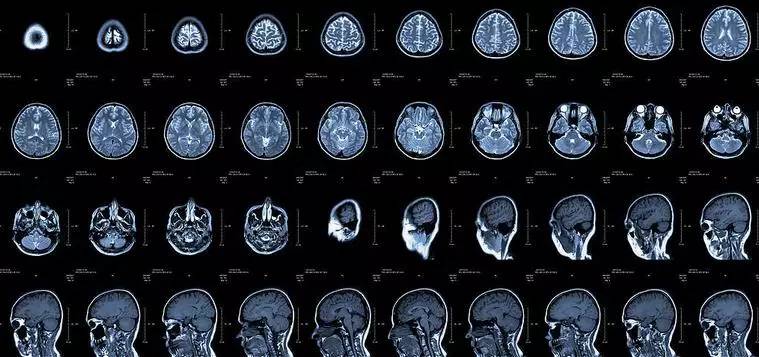

CT:像把面包切片看

CT的檢查原理是X光會分層穿過人體,之后通過電腦計算后二次成像,就像把一片面包切成片來看。優(yōu)點是可以分層看,經(jīng)計算后可以顯示出更多的組織信息。

核磁共振:搖一搖再看

核磁共振機(jī)使用較強大的磁場,使人體中所有水分子磁場的磁力線方向一致,這時磁共振機(jī)的磁場突然消失,身體中水分子的磁力線方向,突然恢復(fù)到原來隨意排列的狀態(tài)。簡單說就相當(dāng)于用手搖一搖,讓水分子振動起來,再平靜下來,感受一下里面的振動。所以,核磁共振(MRI)也被戲說為是搖搖看的檢查。

2、頸椎腰椎——最佳選核磁、次選CT

頸椎病、腰椎間盤突出等椎間盤疾病需要觀察椎間盤與相應(yīng)的神經(jīng)根,要想更好觀察這些軟組織,最優(yōu)選擇就是核磁。同樣,對于關(guān)節(jié)、肌肉、脂肪組織檢查,核磁也是首選。